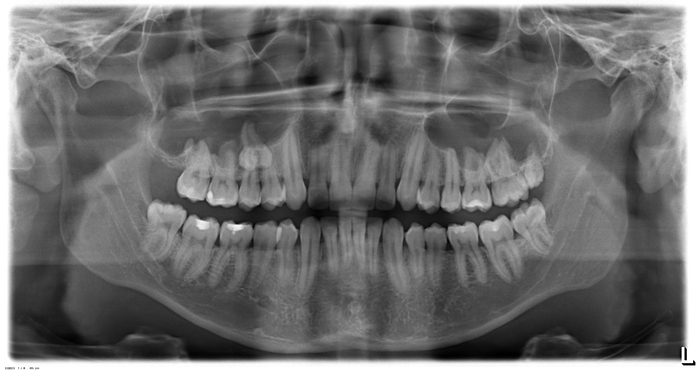

Началось все с того что я решил поставить "брекеты" и обратился к врачу. На тот момент меня ничего не беспокоило, но несколько зубов были очень кривыми. Врач при осмотре обнаружил сверхкомлпектный зуб, он выбивался из зубного ряда и был небольшого размера. Врач отправила меня сделать рентгеновский снимок челюсти, и вот что я обнаружил на нем:

Прошу прощения за качество, но лучшего у меня нет. Снимок был сделан в 2009 году.

Как видно на снимке, в нижней челюсти располагается ДВА сверхкомлпектных зуба. При детальном рассмотрении снимка можно так же рассмотреть справа еще ДВА сверхкомлпектных зуба. ОДИН сверхкомплектный зуб в пазухе слева в корнях 4 и 5 зубов. А так же некоторое искажение снимка слева которое не дает 100% гарантии отсутствия там зубов сверхкомплекта.